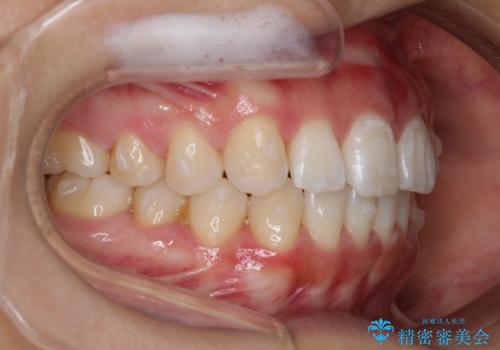

インビザライン矯正 前歯のすきっ歯を治したい

- 上顎の前歯のすきっ歯を治したいとのことで来院されました。

前歯の隙間を閉じる矯正治療の場合、インビザライン適用症例のためインビザラインによる治療をご提案しました。

上唇と歯ぐきを結ぶひも(上唇小帯)が長いと、前歯に隙間が空いてしまうことがあります。今回は隙間を確実に閉じる目的、また矯正後に再び隙間が空かないように、上唇小帯の切除も行っています。